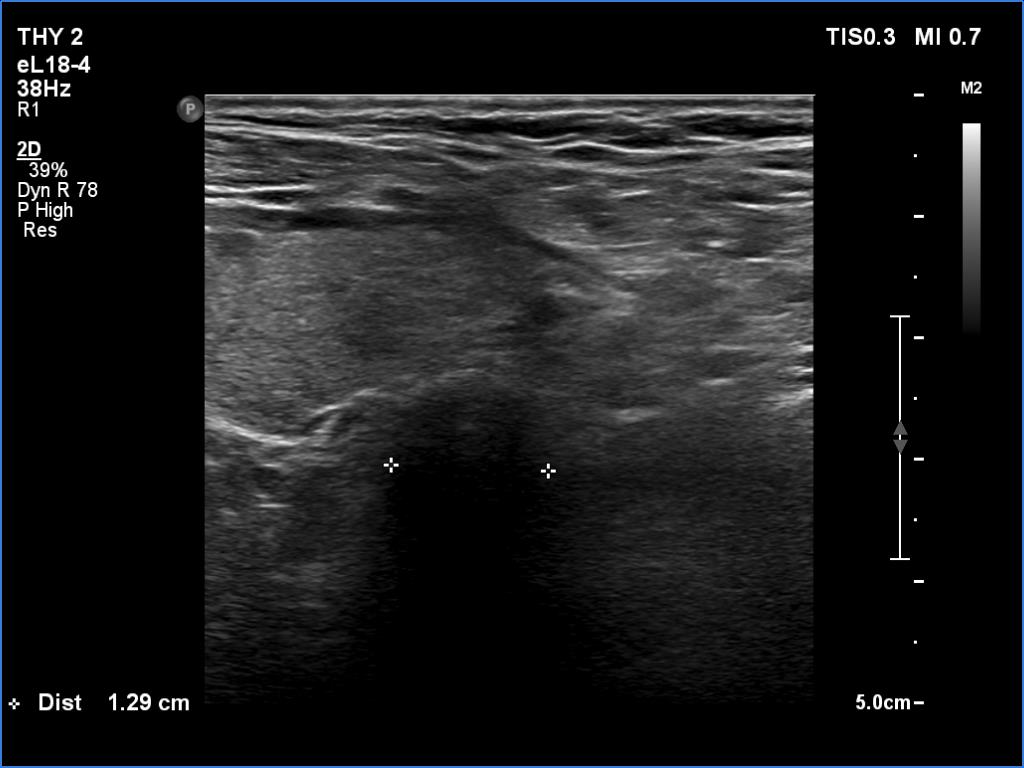

Elastography - case 1260 (ultrasonographic picture 17)

Middle portion of the neck, at the level of the lower pole of the left thyroid lobe. Here the diameter of the trachea is significantly lower.